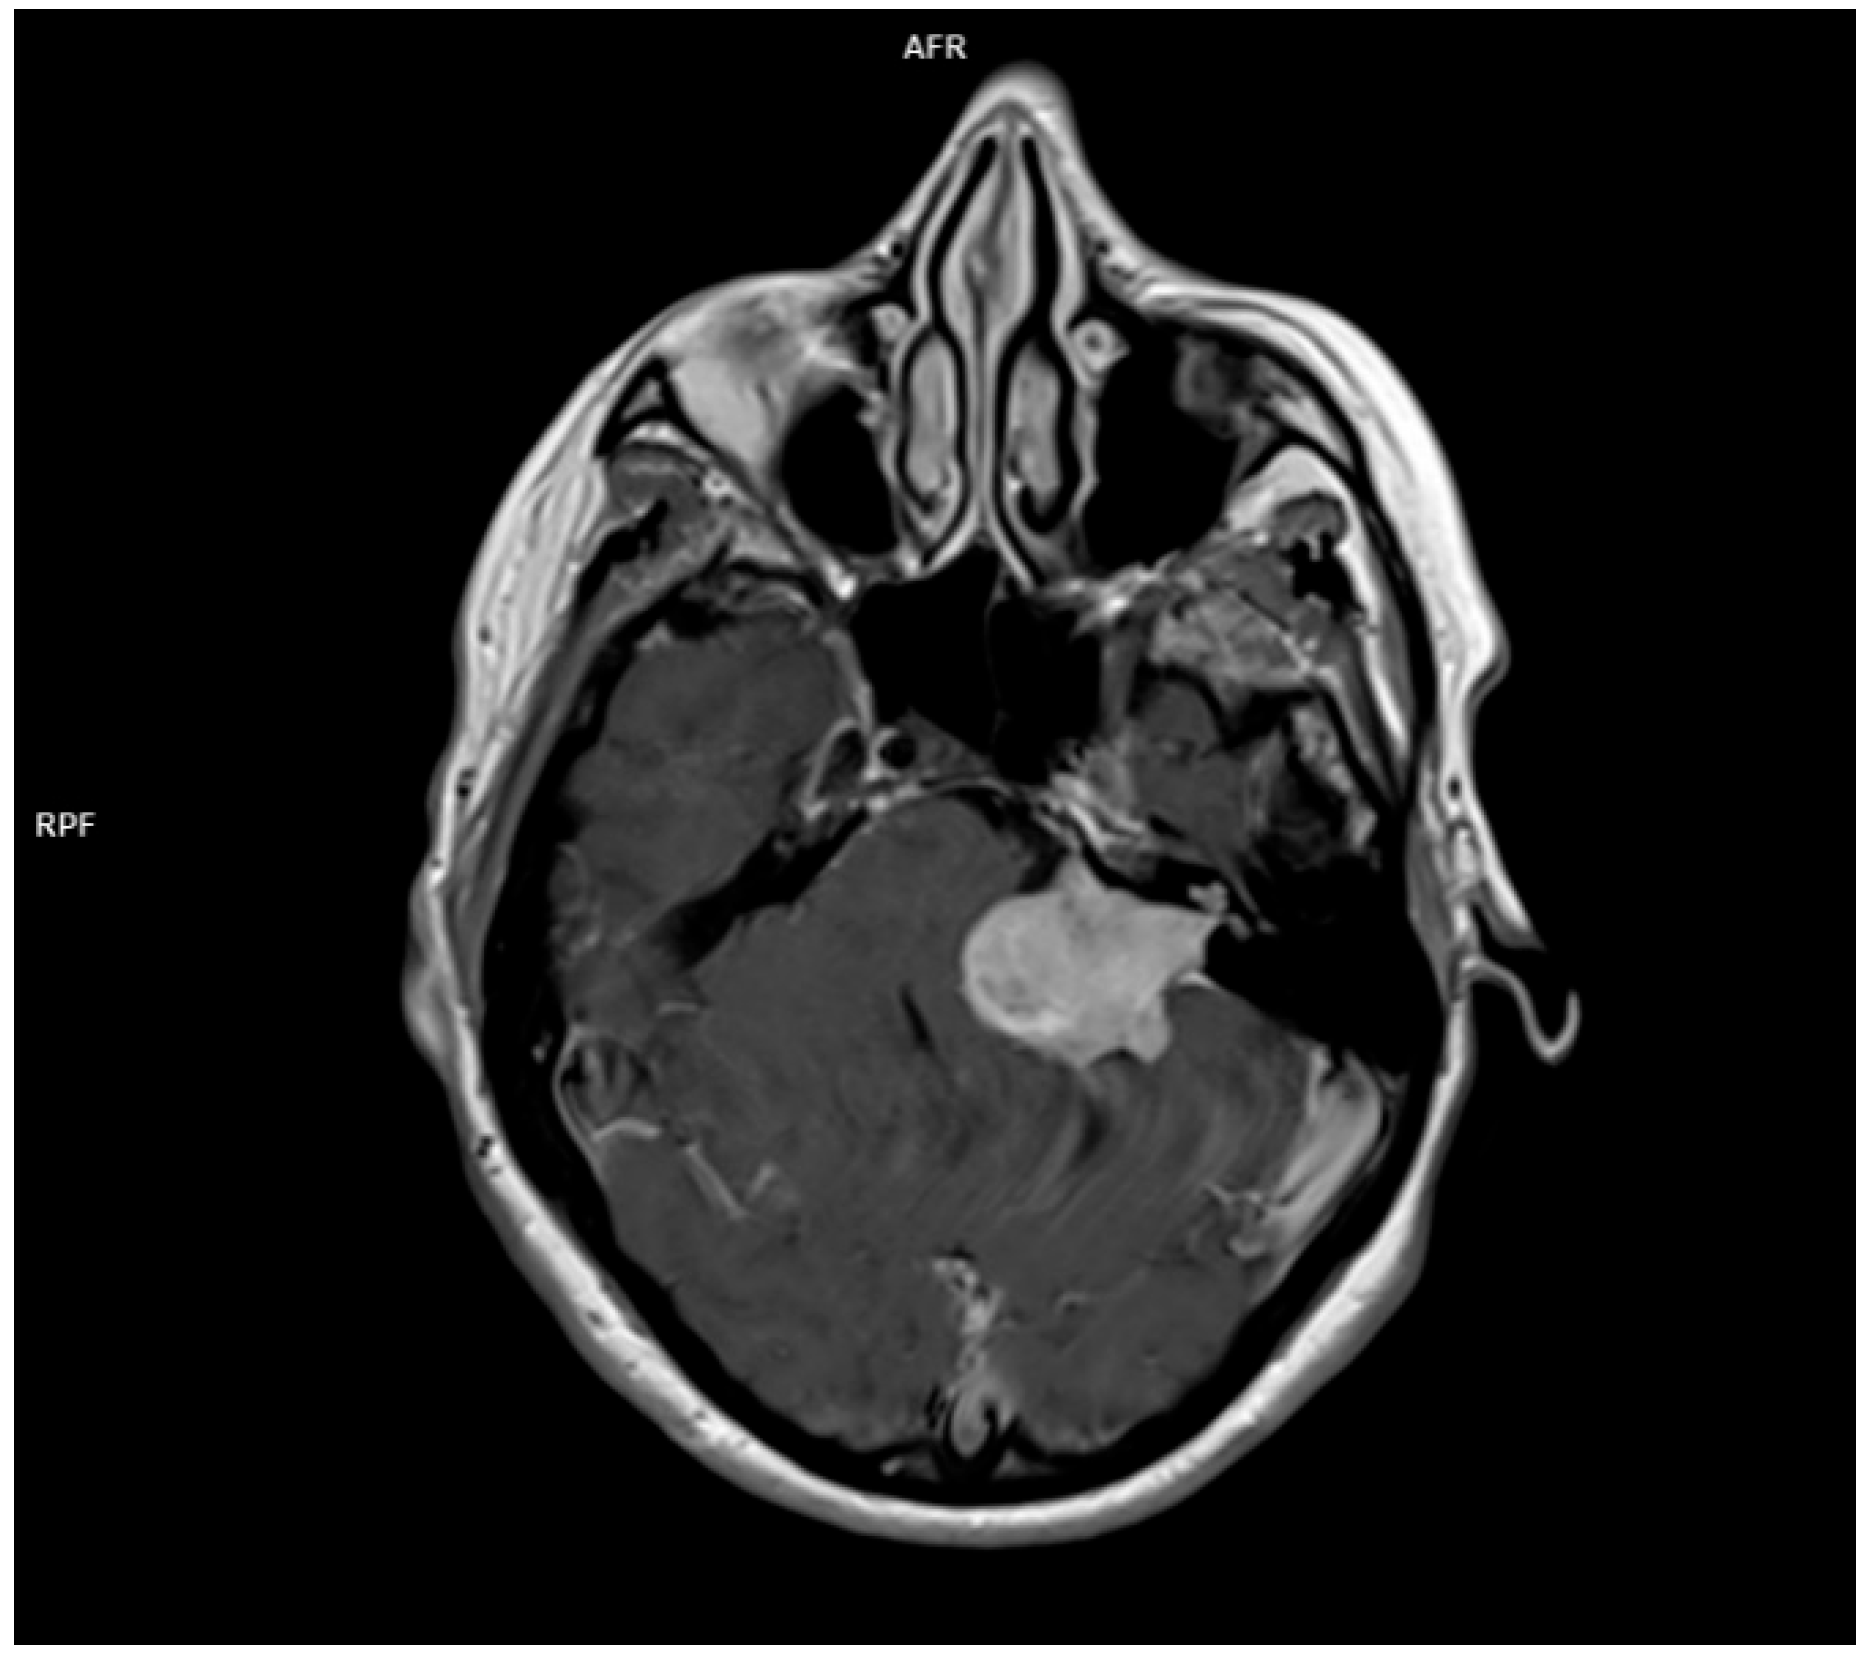

- Datar, S.; Rabinstein, A.A. Cerebellar Hemorrhage. Neurol. Clin. 2014, 32, 993–1007. [Google Scholar] [CrossRef]

- Sankalia, D.; Kothari, S.; Phalgune, D.S. Diagnosing Stroke in Acute Vertigo. Neurol. India 2021, 69, 97–101. [Google Scholar] [CrossRef]